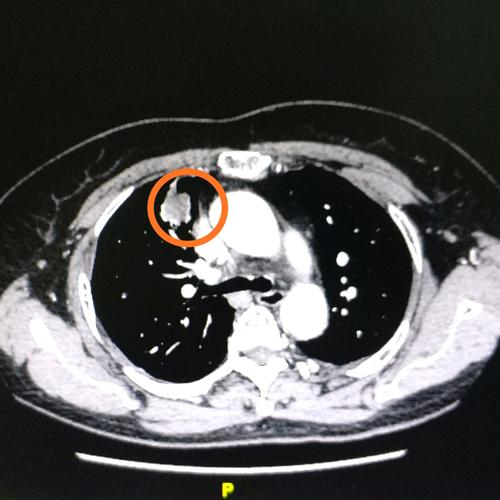

肺肿瘤ct,肺肿瘤

食管癌术后十年,2018年五月份发现肺部转移,七月份再次查ct见肿瘤明显

肿瘤标记物虽然是正常的,但是咳嗽原因不明,ct却发现肺上长了肿物.

实性结节肺部ct影像,仅为举例,非正文所述案例